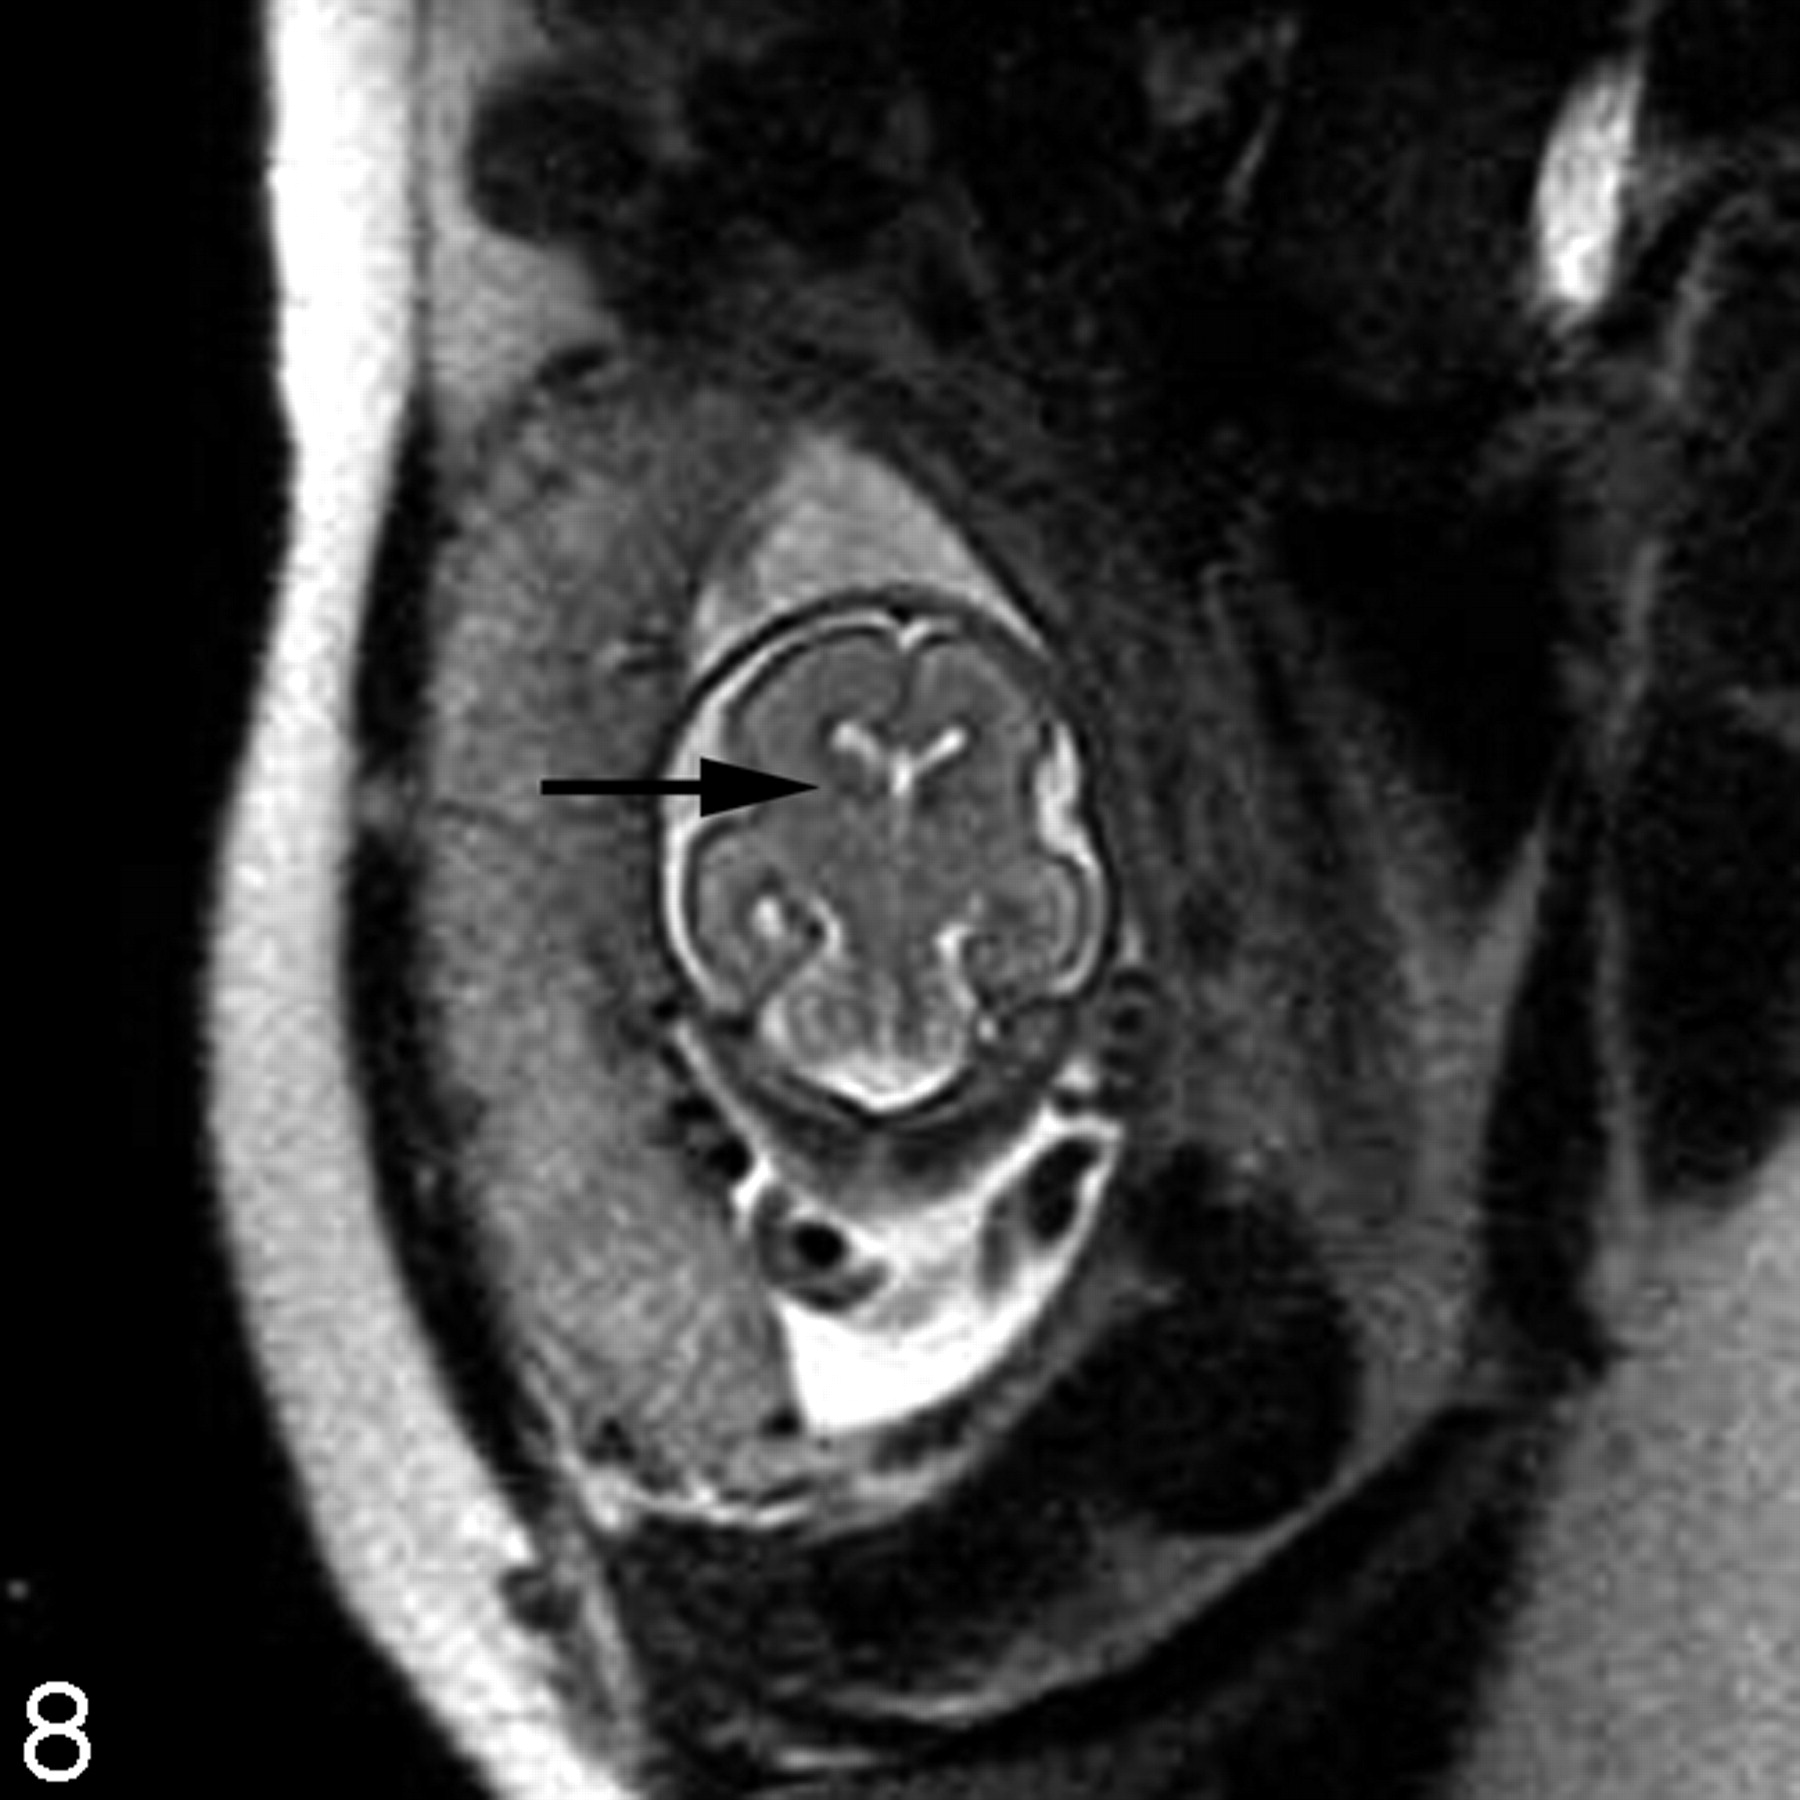

Destructive lesions generally appear as small periventricular areas of T2 hyperintensity, focal defects or irregularities in the germinal matrix, or larger areas of abnormal signal intensity (with or without volume loss) involving the developing white matter and overlying cortex (Fig 7). Subtle irregularities of the ventricular margin may also be an indication of injury to the adjacent germinal matrix and/or overlying developing white matter. Hemorrhage usually appears as a hypointense area on T2-weighted images and hyperintense area on T1-weighted images, though the signal intensity can vary depending on the stage of hemorrhage. Intraventricular hemorrhage can appear as debris layering in the dependent portion of the ventricle or as a focal hematoma (Fig 6B). The detection of small subependymal hemorrhages is more difficult, partly because the normal germinal matrix has similar signal intensity to blood (hypointense on T2-weighted images and hyperintense on T1-weighted images) because of its high cellularity (Fig 8). T2* weighted gradient-echo sequences may be useful to help to confirm the presence of blood, because the hemorrhage appears more hypointense than the germinal matrix.

Coronal ssFSE T2-weighted image in a fetus at gestational week 23 demonstrates prominent hypointensity in the right caudothalamic groove (arrow) consistent with a germinal matrix hemorrhage.